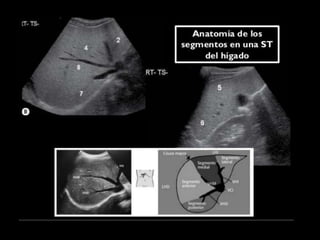

COUINAUD asignó un sistema de numeración para definir la segmentación

hepática.

I – Entre cava y porta

II – el más superior de los izquierdos

III – Por debajo del II

IV – por delante de la vesícula

V – por detrás de la vesícula

VI – relación con riñón derecho

VII – el más posterior de los segmentos superiores

VIII – domo hepático

Las claves de la segm. Hepática